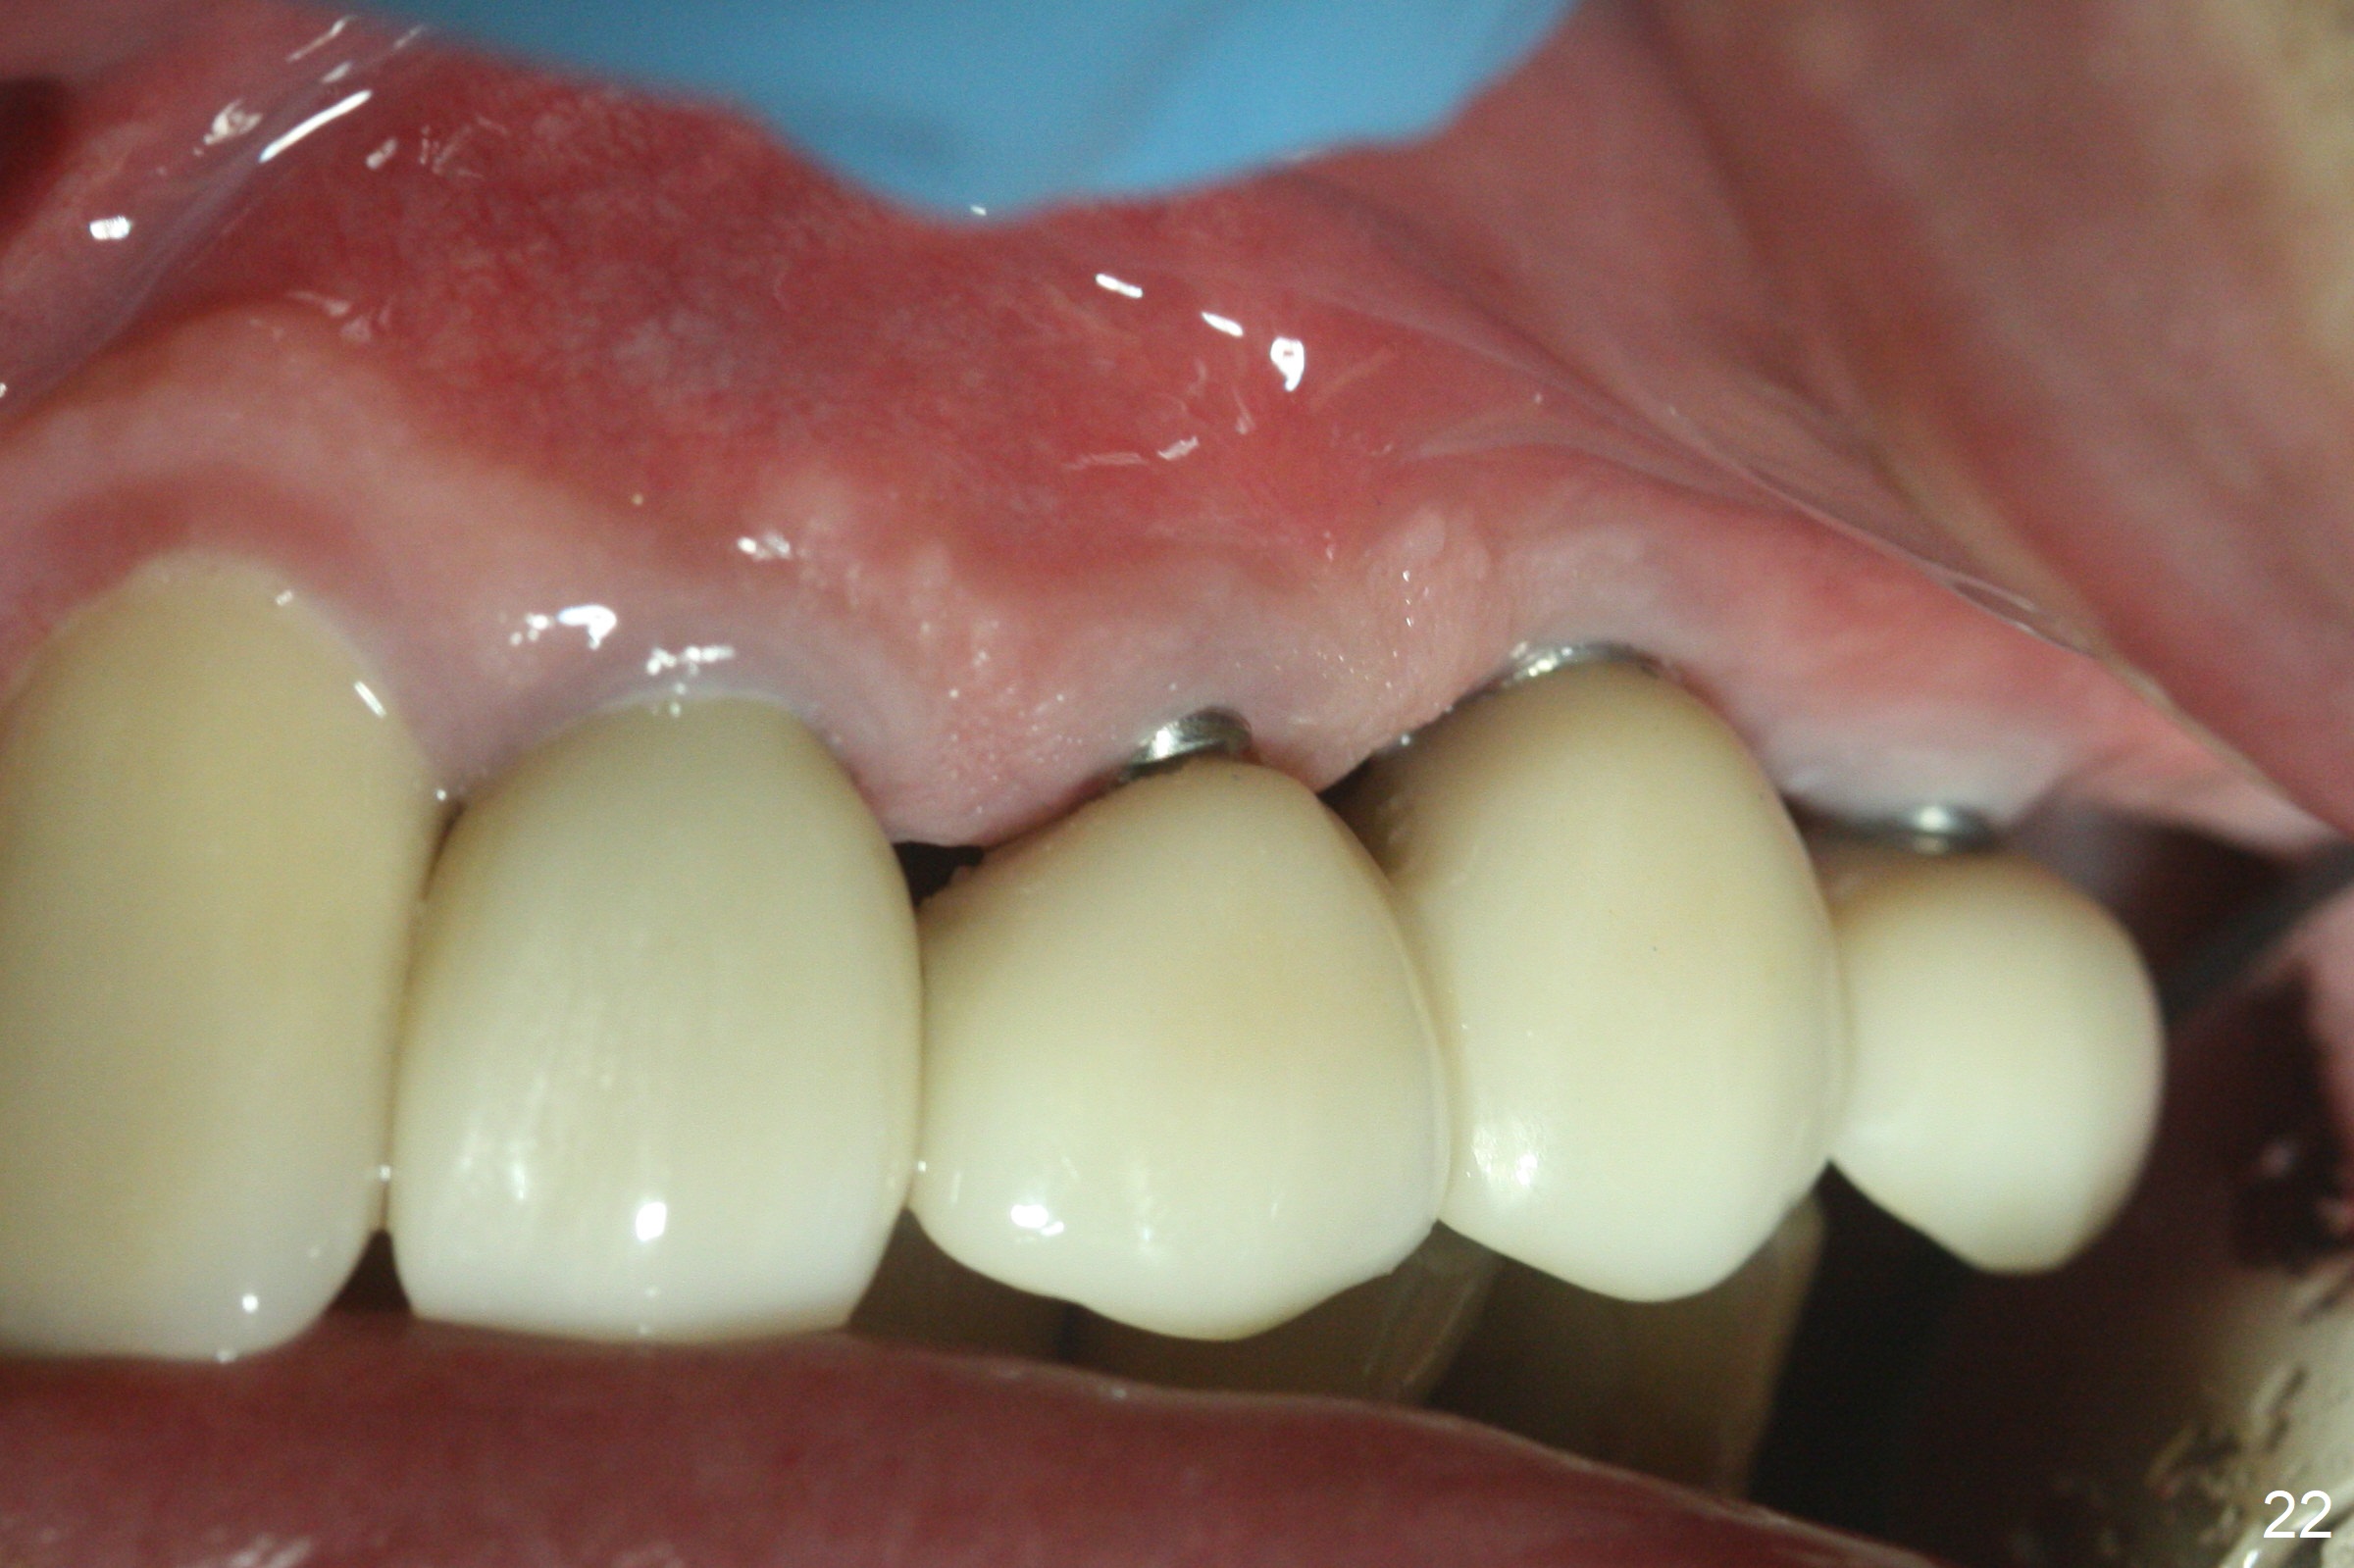

Six months post cementation, the tooth #9 becomes symptomatic.  Is it possible that the implant at #10 is too close to the root of #9?  It is asymptomatic after pulpotomy, but the tooth fractures equi/supragingivally.  Two PAs taken while RCT show osteointegration at #10-12 (Fig.18,19).  While the bone density increases at #10 regular implant, there is minimal bone loss around the 1-piece implants 13 months post cementation (18 months postop, Fig.20,21).  The gingiva remains healthy 19 months post cementation (Fig.22).  76岁病人突然打电话说一个植牙牙冠松动,其实9号牙(自然牙)折裂,6,10-13号牙植牙好像没有骨质吸收(图二十三至二十五),10-13牙位牙龈健康(图二十六,行使功能五年)。9号牙牙冠重新粘固后,显示前牙深覆合,深覆盖(图二十七,二十八)。如果再次脱落需要植牙,选择一段式有助于植入和修复,因为植体和基台直径小。两段式植牙相对基台直径至少4,或者4.5毫米,前牙修复显得笨重。由于9,10牙根和植体接近,9号牙植体需要偏小而长,3x14或者15毫米(图二十九)。